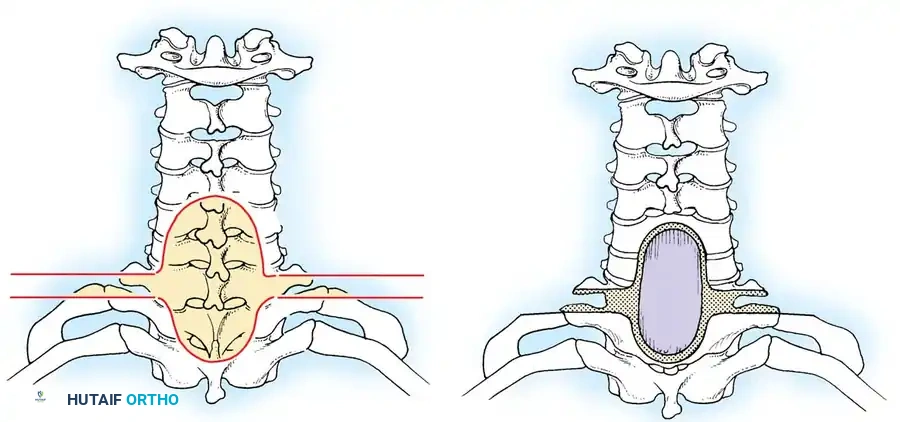

Surgical management of spinal tumors relies heavily on the Enneking classification system, which categorizes benign tumors based on their biological behavior, radiographic margins, and local aggressiveness.

Fig. 41-30: Enneking staging of benign spinal tumors. Capsule of tumor is indicated by 1, and reactive pseudocapsule is indicated by 2. Stage 3 aggressive benign tumors can expand through the posterior vertebral wall and compress the cord. The pseudocapsule is vascularized reactive tissue and can adhere to the dura.

Stage 1: Latent Tumors

These lesions (e.g., asymptomatic osteochondromas, small eosinophilic granulomas) are inactive, well-marginated, and do not progress. They typically require no treatment other than observation. If surgery is mandated for diagnosis or mechanical symptoms, an intralesional excision (curettage) is sufficient.

Stage 2: Active Tumors

Stage 2 tumors (e.g., osteoid osteoma, standard osteoblastoma, aneurysmal bone cysts) grow slowly and cause symptoms, usually pain or deformity. They possess a reactive pseudocapsule. Treatment usually involves en bloc excision where anatomically feasible, though meticulous intralesional excision combined with local adjuvants (liquid nitrogen, phenol, or polymethylmethacrylate [PMMA]) often suffices.

Stage 3: Aggressive Tumors

Despite being histologically benign, Stage 3 lesions (e.g., giant cell tumors, aggressive osteoblastomas) are locally destructive. They breach the tumor capsule, invade local compartments, and have a high propensity for recurrence.

Wide excision—removal of the tumor with a continuous cuff of normal, healthy tissue—is the oncologic treatment of choice. A marginal excision (dissecting through the reactive pseudocapsule) leaves microscopic disease and results in unacceptably high recurrence rates.